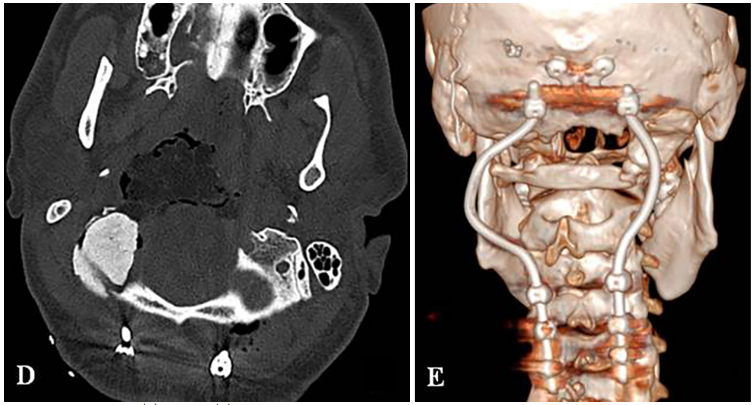

固定根钉以曲线方式横向弯曲,为后续质子治疗创造一个无金属的定位及治疗通道。术后CT和MRI显示肿瘤完全切除。病理证实为典型脊索瘤。在术后恢复中,患者吞咽功能改善和颈部疼痛缓解。8周后,他接受了质子治疗。

▼D:术后CT显示PMMA枕髁重建稳定良好。E:术后三维CT显示C0-C3-C4-C5枕颈融合稳定,与根钉弯曲有利于PBRT治疗。

福教授在颈椎的C0、C3、C4和C5椎体上分别开孔,以便植入根钉。这些根钉在设计上独具匠心,采用了曲线方式横向弯曲,使其能够更好地适应颈椎的生理曲度。这种固定方式不仅能提高固定效果,还能减少对周围软组织的损伤。

在植入根钉后,福教授使用Roy-Camille技术进行枕颈融合术(C0-C3-C4-C5)。融合过程中,使用生物材料填充椎体之间的空隙,以促进骨组织的生长和愈合,从而提升颈椎的稳定性。